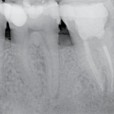

Preoperative x-ray: Upon diagnosis of pulp necrosis an initial endodontic treatment is indicated. The mesial root canals present a mineralized root canal lumen and a strong curvature and the distal canal an extremely curved apical third.

Postoperative x-rays: The endodontic treatment is performed after scouting of the root canal with a diameter 10 hand file and securing of the mesial root canals using the NiTi file One G. Shaping was carried out with TS1 and TS2 to the working length, the MB2 canal was prepared using…